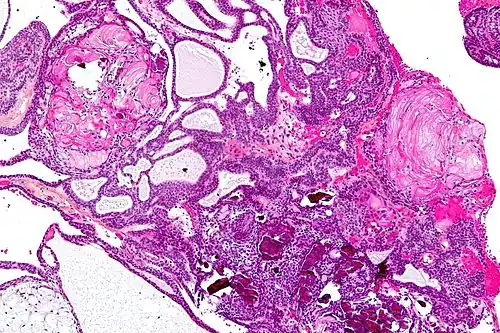

The papillary type rarely calcifies. A vast majority of craniopharyngiomas in children are adamantinomatous, whereas both subtypes are common in adults. Mixed-type tumors also occur.[25]

On macroscopic examination, craniopharyngiomas are cystic or partially cystic with solid areas. On light microscopy, the cysts are seen to be lined by stratified squamous epithelium. Keratin pearls may also be seen. The cysts are usually filled with a yellow, viscous fluid rich in cholesterol crystals. Of a long list of possible symptoms, the most common presentations include headaches, growth failure, and bitemporal hemianopsia.

-

Micrograph showing a papillary craniopharyngioma, HPS stain